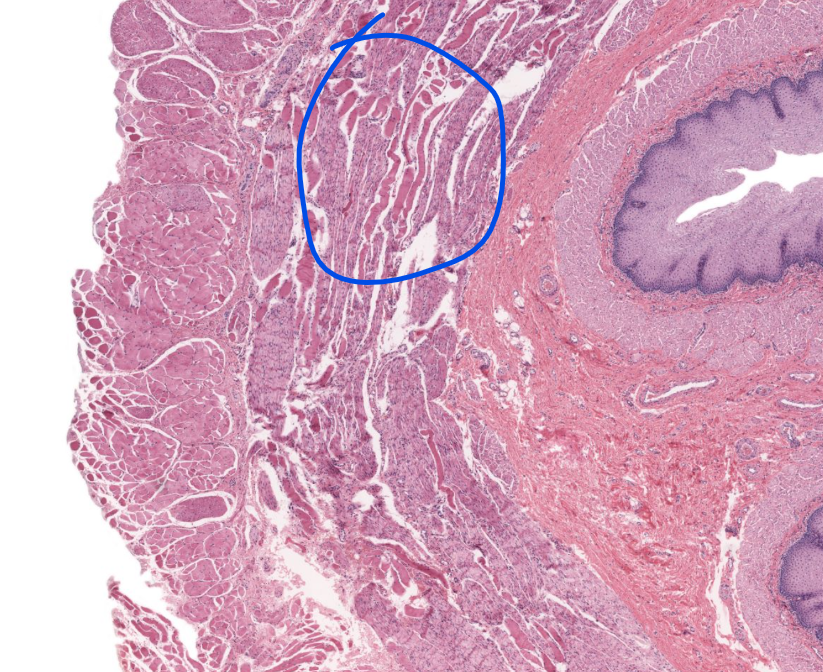

esophagus

layer

submucosa of the esophagus

submucosal glands!

muscularis externa of esophagus

specific layer

inner layer muscularis externa of esophagus

outer layer muscularis externa of the esophagus